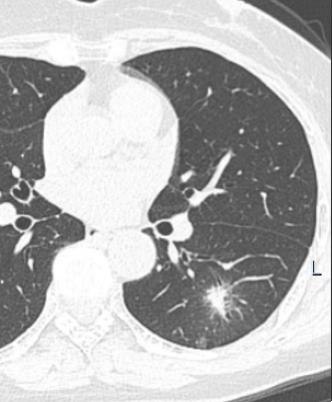

2023年6月16日,对于65岁的林女士及家人来说是个无比灰暗的日子,体检CT结果显示林女士左下肺背段有一约29×16mm(核桃大小)结节影,边缘模糊,有长毛刺,考虑肺部恶性病变,医生建议尽快进行手术治疗,这对于林女士一家人来说无异于晴天霹雳。

2016年6月16日(体检发现左下肺结节)